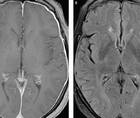

Symptoms of Lewy Body Dementia Induced by Herpes Zoster Encephalitis

Ryan Verity, MD; Andrew Kirk, MD, FRCPCRyan Verity, MD; Andrew Kirk, MD, FRCPC - Alzheimer Disease & Dementias